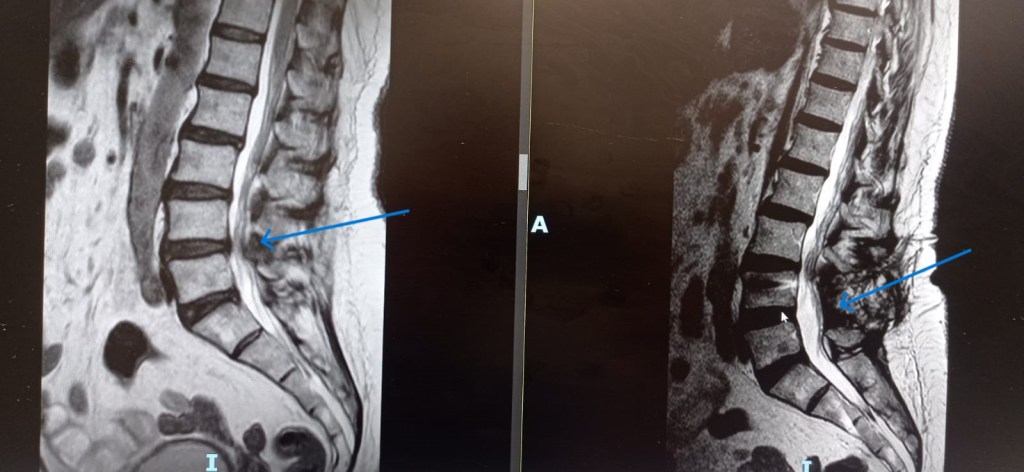

–Fracturas vertebrales: Frecuentes sobre todo en la columna dorso-lumbar, pueden aparecer como consecuencia de mecanismos muy diversos; desde grandes traumatismos, en cuyo caso su tratamiento puede estar condicionado por la presencia de otras lesiones, o bien tras traumatismos banales o incluso de forma espontánea, sin traumatismo alguno. Estos últimos casos definen las «fracturas patológicas» en las que es preciso buscar una causa subyacente estructural o sistémica que haya provocado el debilitamiento óseo. Esta situación es especialmente frecuente en mujeres tras la menopausia debido al desarrollo de osteoporosis. Estos casos precisan iniciar un tratamiento para compensar la desmineralizacón ósea. El tratamiento de las fracturas depende fundamentalmente del grado de deformidad asociado, la afectación de ligamentos (ambos aspectos definen la presencia o no de inestabilidad) y el que exista o no una lesión neurológica. En caso de fracturas estables sin déficit neurológico se emplea una ortesis mientras que en presencia de inestabilidad o afectación neurológica debe valorarse la cirugía.

-Tumores espinales: Dan lugar a una gran variedad de situaciones debido a que pueden afectar a diferentes compartimentos: óseo (tumores primarios ó metástasis con o sin extensión al canal raquídeo; siendo los hemangiomas los más frecuentes), intradural-extramedular (los más frecuentes meningiomas y algunos neurinomas) e intradural-intramedular (astrocitomas y ependimomas). Suelen manifestarse con dolor, alteración de la sensibilidad y/o fuerza en las extremidades acompañada o no de alteración esfinteriana. Van a precisar cirugía en caso de que generen inestabilidad vertebral, déficit neurológico o muestren un comportamiento agresivo.